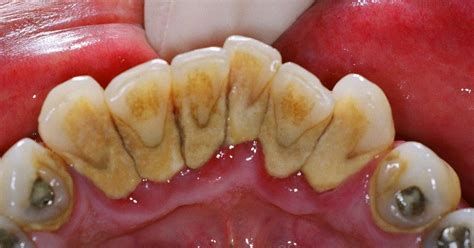

El sarro, también conocido como cálculo dental, es un problema bucodental muy frecuente que consiste en la calcificación de la placa bacteriana o placa dental.

La placa es una película pegajosa compuesta por restos de comida, bacterias y saliva. Cuando no se elimina adecuadamente mediante el cepillado y el uso de hilo dental, la placa se mineraliza debido a los minerales presentes en la saliva, formando sarro.

- Proximidad a las glándulas salivales: Los dientes inferiores, especialmente los incisivos y caninos, están muy cerca de las glándulas salivales submandibulares y sublinguales.

- Gravedad y flujo salival: La saliva tiende a acumularse en la parte inferior de la boca debido a la fuerza de la gravedad.

Cuando la placa no se elimina adecuadamente mediante el cepillado y el uso del hilo dental, se mineraliza y se convierte en sarro.